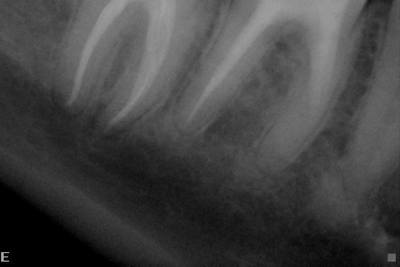

Через месяц протезированный 47й зуб заболел заболел и я обратилась в клинику номер 2. Мне сделали снимок 47го зуба, который показал воспалительный процесс в области верхушек корней. Дабы исключить сомнения, я съездила и сделала компьютерную томографию 47го зуба. КТ показала воспаление не только в области верхушек, но и между корнями зуба.